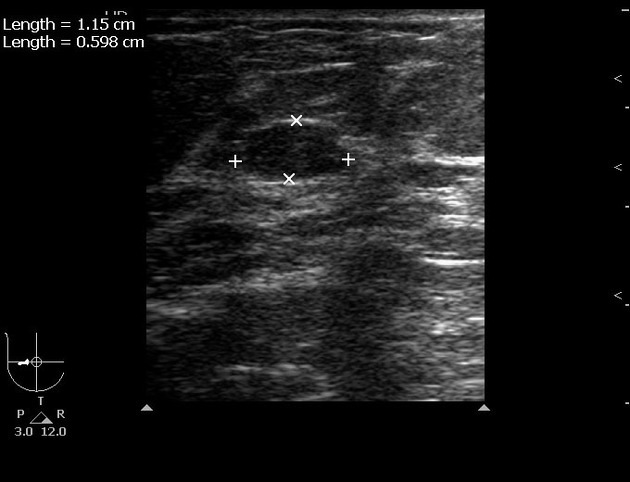

Ultrasound revealed an irregular hypoechoic lesion of 3 cm, with marked posterior acoustic shadowing (the lesion was considered as BI-RADS 5).

Echo color Doppler shows a peripheral straight vessel penetrating the lesion, but no internal vessels.

Usually subareolar or central breast

US: Hypoechoic region/mass with indistinct margins, marked posterior shadowing without internal flow

Hypoechoic, avascular shadowing mass with indistinct margins

Ultrasonographic Findings

Hypoechoic region or mass with indistinct or spiculated margins and marked posterior shadowing

Typically avascular on color/power Doppler